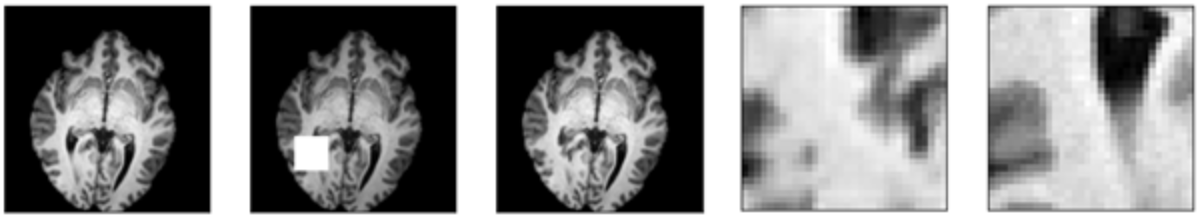

As shown in figure 2, one can see how the problem definition changed according to the amount of data masked. For smaller window sizes, the inpainting network is only required to reconstruct a handful of pixels. However, with larger masks the network is required to reconstruct texture and structure. Additionally, due to adversarial training, the network produces reconstructions without blur.